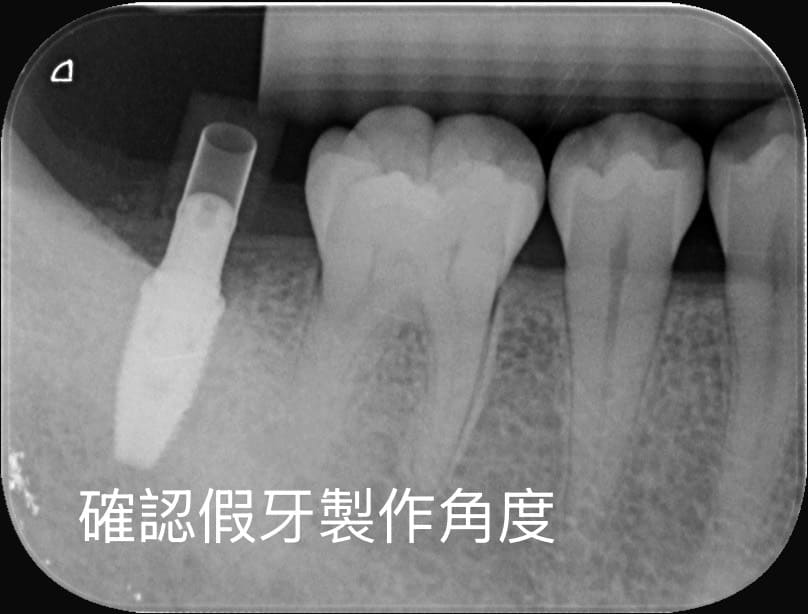

電腦模擬植牙位置

在手術前先透過軟體模擬植體角度與位置,降低手術誤差。

這些數位技術能讓植牙規劃更精準,也能幫助醫師提前預判風險。